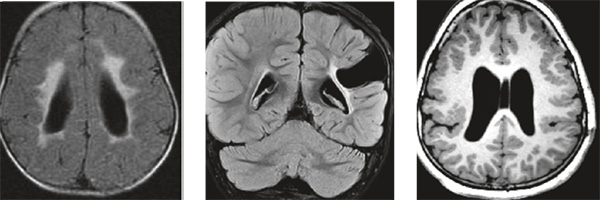

头MR显示脑部非进行性损伤(缺血缺氧变、脑梗塞及脑发育异常)。